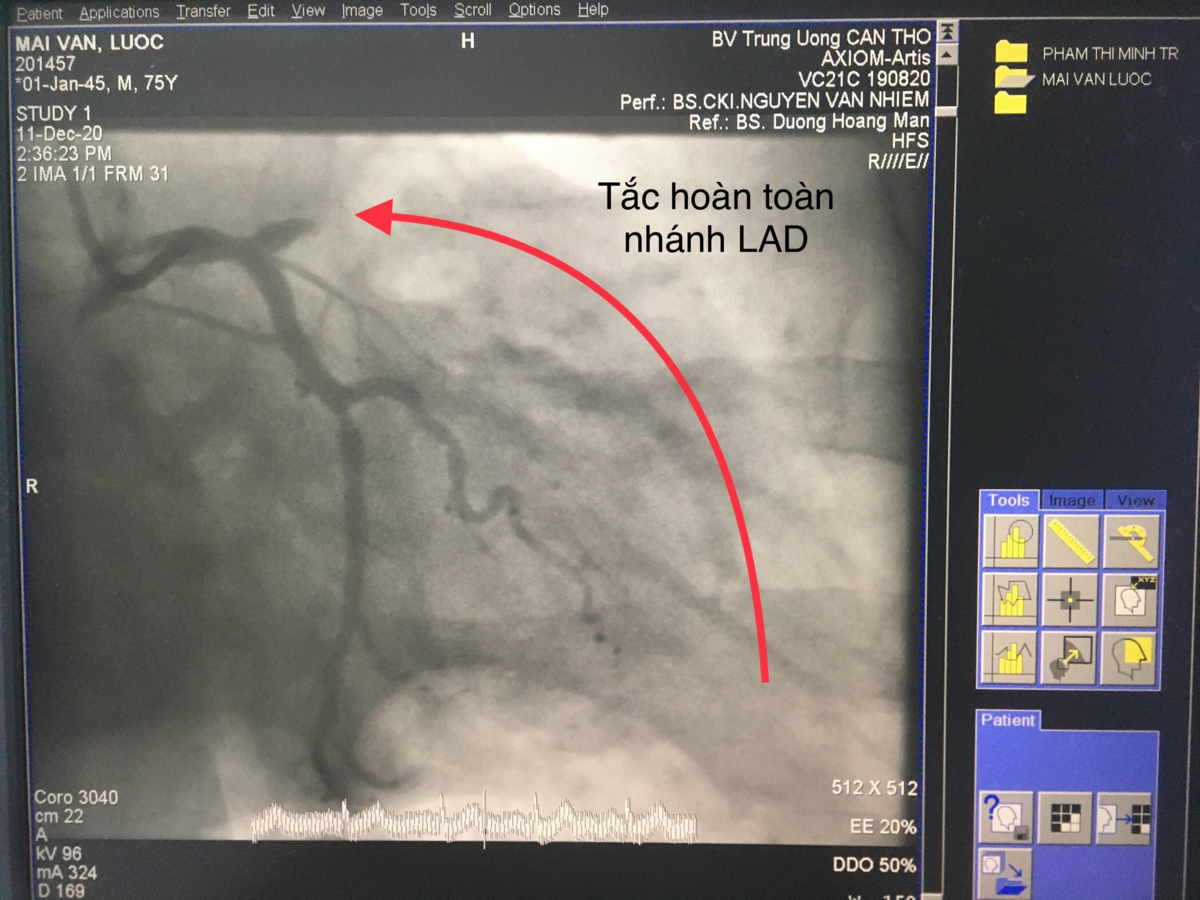

Hình ảnh động mạch vành của bệnh nhân nhồi máu cơ tim cấp trước khi được bác sĩ can thiệp.

Bs.CK2 Phạm Thanh Phong - Phó Giám đốc chuyên môn, Giám đốc Trung tâm tim mạch Bệnh viện Đa khoa Trung ương Cần Thơ cho biết, nhồi máu cơ tim là tình trạng tắc hoàn toàn một hoặc nhiều nhánh động mạch vành - động mạch cung cấp máu nuôi tim một cách đột ngột, làm chết tế bào cơ tim.